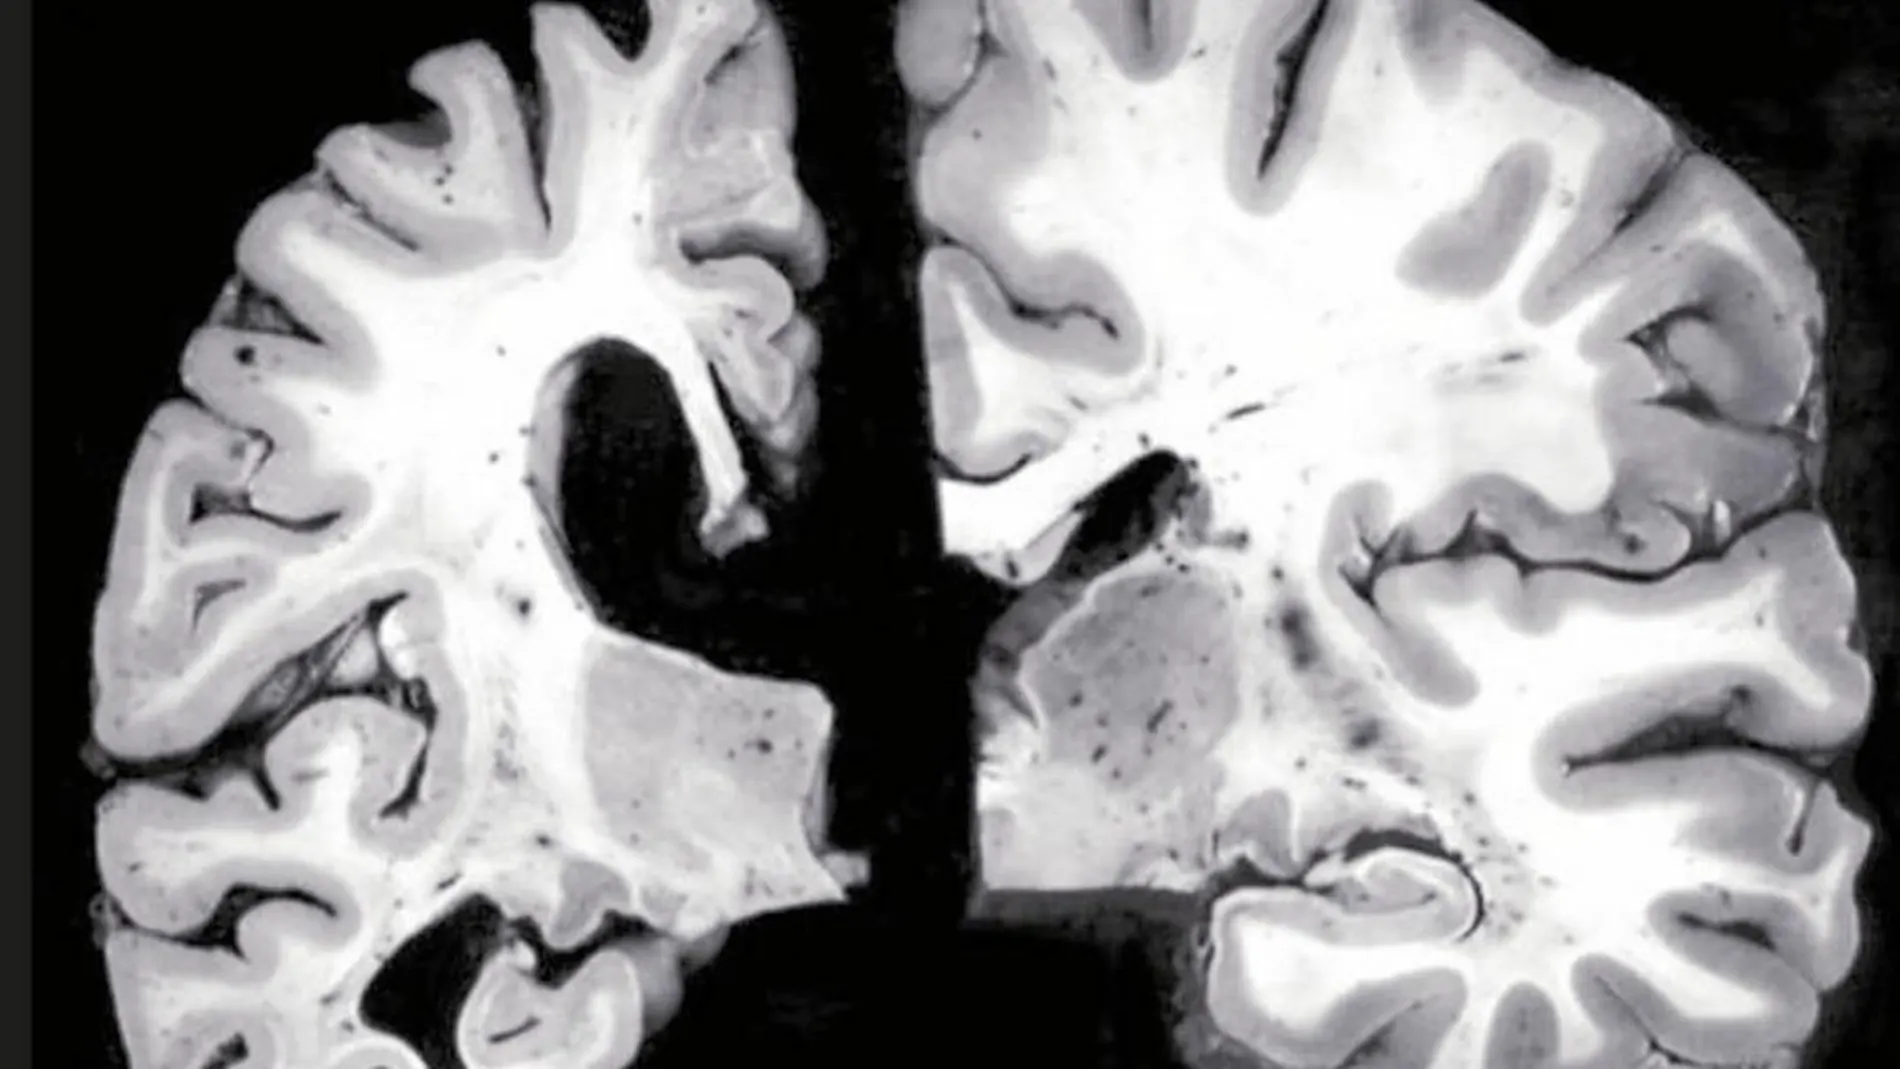

BACE es el nombre de una enzima que hasta esta semana puede que sólo fuera conocida en los círculos más especializados de la investigación biomédica. Ahora se ha convertido en protagonista de dos noticias antagónicas. La molécula vivió el pasado jueves los sinsabores del mayor «cara y cruz» desde que se investiga con ella. La compañía farmacéutica Merck anunció que ha decidido cancelar la fase III del ensayo clínico que venía realizando con una prometedora terapia contra el Alzheimer. Se trata de un fármaco inhibidor de la acción de la enzima BACE1 llamado verubecestat. Se sabe desde hace tiempo que esta enzima está implicada en la formación de proteína beta-amiloide. Precisamente la acumulación inusual de ésta genera un efecto tóxico en las neuronas que conduce al desencadenamiento de la enfermedad de Alzhéimer. Bloquear la acción de BACE1 parecía una buena idea para tratar de retirar el exceso de proteína perjudicial y recuperar la función cognitiva sana de los pacientes.

Los expertos saben que este mal es uno de los más complejos de abordar. El foco principal de la investigación es el tratamiento de la acumulación de las proteínas beta-amiloide y tau (dos de los grandes causantes del Alzheimner), pero en el desarrollo de la patología pueden influir otros factores tan difusos como la salud vascular, la inflamación, el estilo de vida e, incluso, según algunas propuestas, la exposición a ciertos virus. ¿Cómo se aborda un abanico tan amplio de factores?

Y aquí es donde llega la buena noticia. Porque un equipo de investigadores del Cleveland Clinic Lerner Research Institute ha descubierto que la eliminación gradual de una modalidad de la enzima BACE1 es capaz de revertir totalmente la acumulación de placas de proteína beta-amiloide en ratones con alzhéimer y podría reducir el peligro de efectos secundarios. Como consecuencia de ello, la salud cognitiva de los animales mejora sustancialmente. Los investigadores han desarrollado ratones que gradualmente perdían la capacidad de producir esa enzima. Los animales crecieron de manera sana y permanecieron así durante un largo periodo de tiempo. Después, cruzaron estos ratones con otros que habían desarrollado placas de beta-amiloide a partir de los 75 días de edad. Los descendientes de estos cruces nacieron con una mayor propensión a acumular placas de beta-amiloide que los ratones sanos, pero sus niveles de BACE1 eran un 50 por ciento menores de lo normal. Con el tiempo, las placas de proteína perjudicial fueron desapareciendo. Al hacerlo, las capacidades de aprendizaje y memoria de los animales mejoraron considerablemente. Es la primera vez que se observa una reducción tan drástica de la beta-amiloide acumulada una estrategia interesante para combatir el alzhéimer.